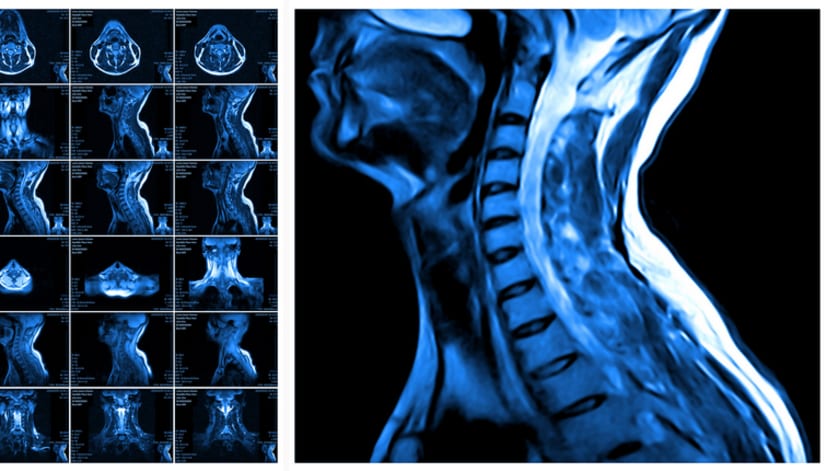

March 23, 2026 MRI Identifies 3 Friedreich Ataxia Subtypes Machine learning analysis of structural MRI reveals distinct patterns of neurodegeneration that vary in their association with disease severity Conexiant

March 19, 2026 Lumbar Fusion: Two Decades of Change Investigators find rising use of complex lumbar fusion procedures and increasing hospital costs in the US. Conexiant

March 18, 2026 Penetrating Neck Trauma Triage Shifts CT angiography and clinical signs refine triage and management. Conexiant